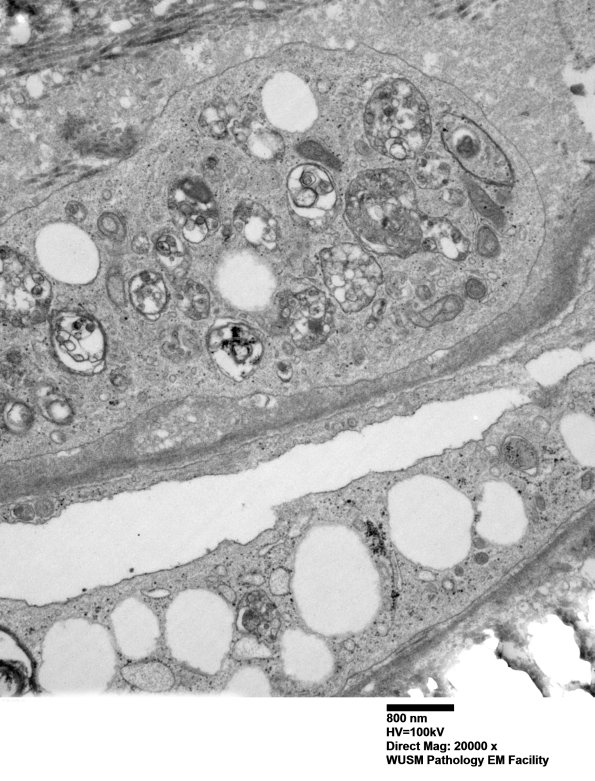

2D3,4 These are most likely autophagic vacuoles in the perineurial interstitium. (electron micrographs)